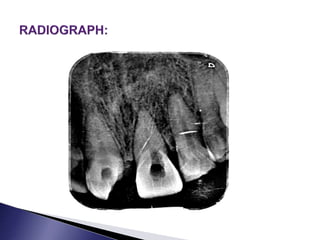

 PATIENT DETAILS: NAME: X  AGE/SEX: 25yrs/ male  ADDRESS: Madurai  OP NO: 19- 00625  DATE REPORTED: 11.01.19

• 64.

 Patient reportedto the department with a complaint of discoloured tooth in the upper front region of the jaw  History of unesthetic appearance

• 65.

 History oftrauma before 2 years  There was no relevant medical history  Patient has normal food habits, and brushes twice daily using brush and paste  Patient is alert, cooperative, conscious and well-oriented

• 66.

 Facial symmetrypresent  TMJ is normal  Cervical lymph nodes not palpable  There is no extraoral swelling evident

• 67.

 Discoloured 11 Fractured 21, ellis class 111  Tender on percussion present in 11,21  No swelling evident  No sinus tract or abscess evident

• 69.

 NO responsein 11  Immediate exaggerated response,pain in 21

• 70.

 Calcific metamorphosisin 11  Symptomatic pulp with irreversible pulpitis in 21

• 71.

 Root canaltreatment in 11,21